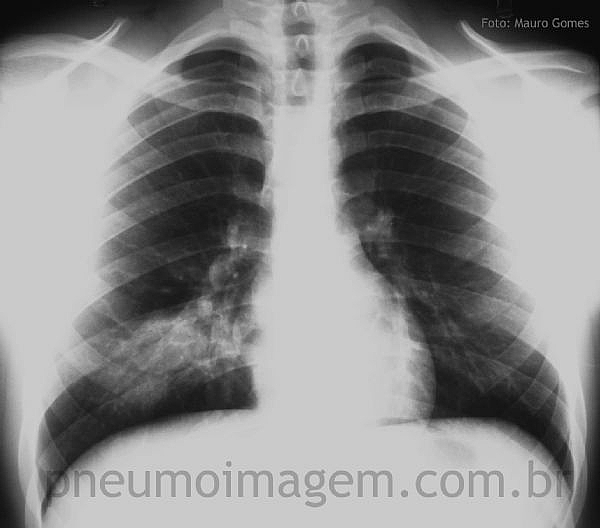

Veja imagens de pneumonia por S. aureus no PneumoImagem, clique aqui.